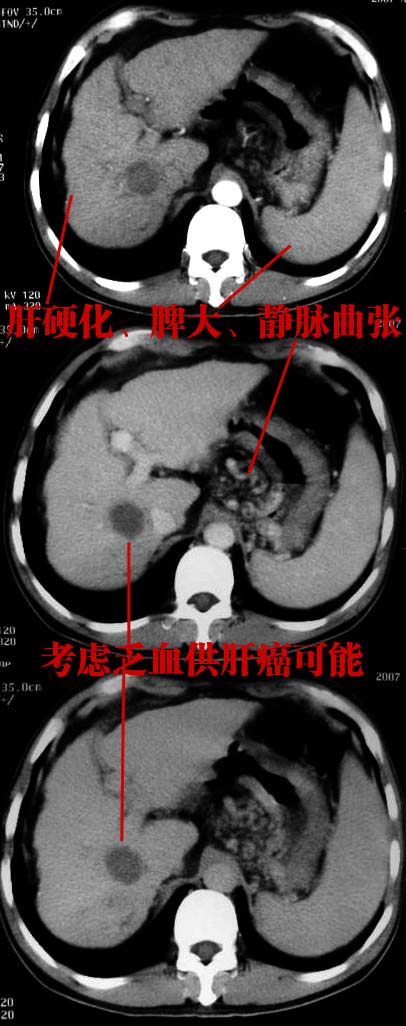

肝硬化 脾大 胃底静脉曲张 肝癌 门腔间淋巴结肿大

肝癌、肝硬化、脾大、门静脉高压、胃底静脉曲张.

肝硬化、脾大,静脉曲张,肝右叶低密度灶,增强无明显强化,还是考虑肝癌可能性大,建议结合afp检查。

考虑肝硬化,脾大,静脉曲张,肝右叶低密度灶,右肝癌可能性大。

肝癌分为肝细胞性和胆管细胞性,从强化表现来看,确切地说应是胆管细胞癌.